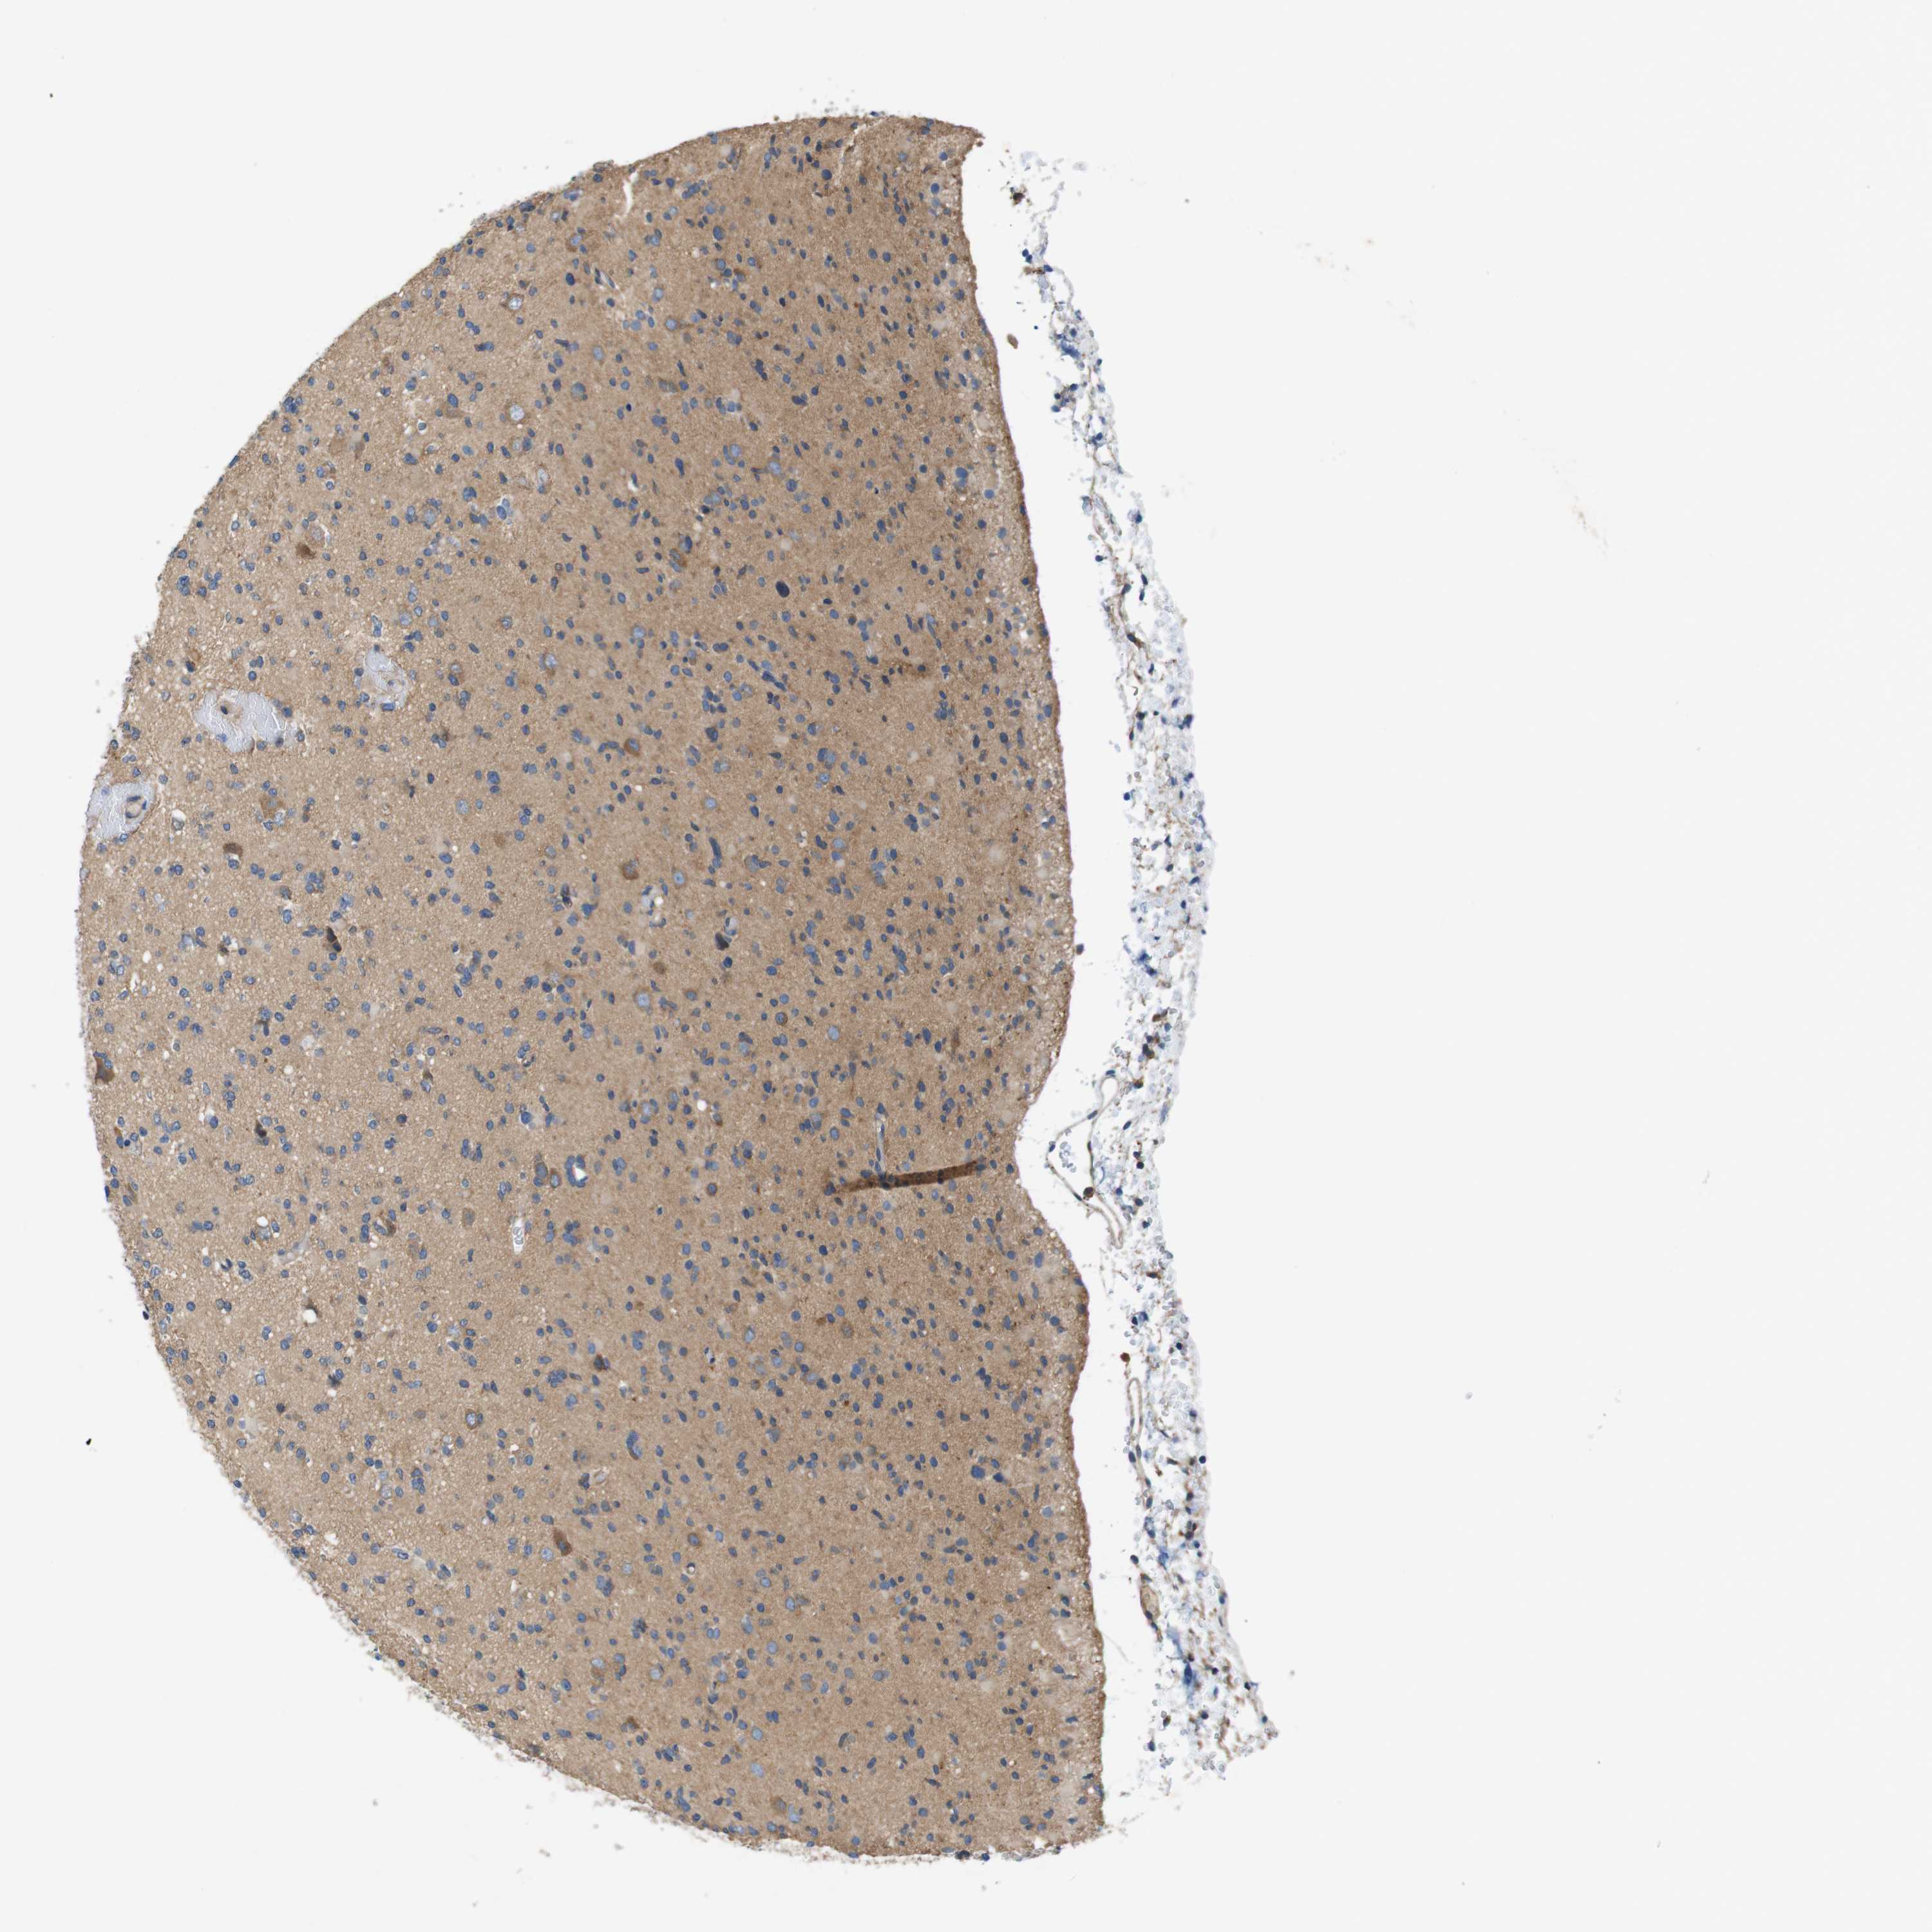

GLIOMA - Protein expressioni

A mouse-over function shows sample information and annotation data. Click on an image to view it in a full screen mode. Samples can be filtered based on level of antibody staining by selecting one or several of the following categories: high, medium, low and not detected. The assay and annotation is described here.

Note that samples used for immunohistochemistry by the Human Protein Atlas do not correspond to samples in the TCGA dataset.

Antibody stainingi

Antibody staining in the annotated cell types in the current human tissue is reported as not detected, low, medium, or high, based on conventional immunohistochemistry profiling in selected tissues. This score is based on the combination of the staining intensity and fraction of stained cells.

Each image is clickable and will lead to virtual microscopy that enables deeper exploration of all samples and also displays staining intensity scores, fraction scores and subcellular localization as well as patient and tissue information for each sample.

Antibody HPA034635

Antibody HPA069977

Antibody HPA071875

Antibody CAB009108

Staining

High

Medium

Low

Not detected

Intensity

Strong

Moderate

Weak

Negative

Quantity

>75%

75%-25%

<25%

None

Location

Nuclear

Cytoplasmic/membranous

Cytoplasmic/membranous,nuclear

Glioma, malignant, Low grade

Glioma, malignant, High grade